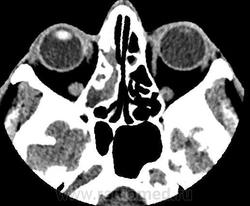

По задней стенке правой половины лобной пазухи определяется выбухание патологического содержимого в полость передней черепной ямки с наличием реактивного утолщения надкостницы ~на 5 мм. При контрастном усилении наблюдается интенсивное накопление контрастного вещества толстой стенкой отграниченного образования, содержимое пазух не накапливает контрастный препарат.

- определяется участок пониженной плотности в полюсно-базальных отделах правой лобной доли (+25+30Hu), являющийся зоной энцефалита, без четких контуров, не накапливающий контрастный препарат при контрастном усилении.

Заключение: КТ признаки полисинусита, осложненного хроническим остеомиелитом стенок гайморовых и обоих половин лобной пазухи, ячеек решетчатого лабиринта справа, наличием участков деструкции стенок обоих половин лобной пазухи, зоны энцефалита в полюсно-базальных отделах правой лобной доли. Полипы передне-верхней стенки левой половины основной пазухи, среднего носового хода справа. Признаки ороантрального свища слева.

С контрастом: